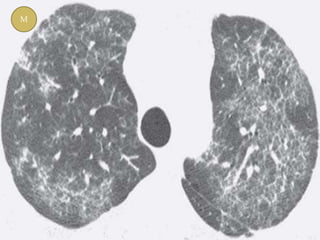

M

 Abnormalities seen on HRCT in NSIP can

mimic with :-

(a) UIP (predominantly lower lobe reticulations)

(b) HP, RB-ILD (predominantly GGO)

(c) BOOP(when there is extensive consolidation)

 Multivariate logistic regression analysis

showed that the most useful finding for

distinguishing IPF from NSIP was the extent of

honeycombing. The average extent of

honeycombing was 4.4% of parenchyma in IPF

and less than 1% in NSIP.

 Lower lobe predominance

 Traction bronchiectasis

 Subpleural sparing

 Extensive reticulation and

fibrosis